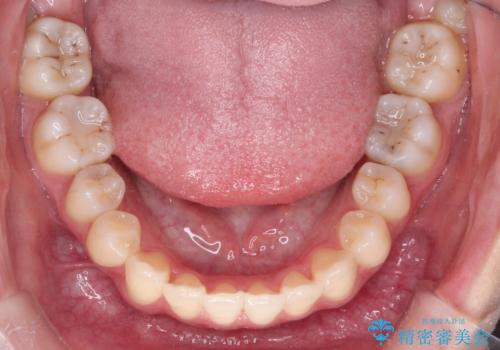

インビザラインによる非抜歯矯正 ガタガタな歯並びを整った歯並びへ

使用時間を守っていただけたので、スムーズに治療を終わることができました。